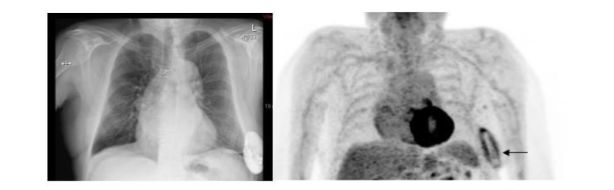

Published data confirm that ¹⁸F-FDG is useful for diagnosing cardiac implantable device infections. This test accurately diagnoses and determines the extent of left ventricular assist device infections and improves the diagnostic accuracy of the modified Dukes Criteria (Figure 14)⁴⁶–⁴⁹.

Figure 14.

Infected Cardiac Defibrillator. The abnormal ¹⁸F-FDG activity is confined to the pocket (arrow). The device and leads were removed, and the infection was confined to the pocket; the leads were not involved.

In a meta-analysis of nearly five hundred patients, the pooled sensitivity and specificity of ¹⁸F-FDG PET/CT for diagnosing these infections were 83% and 89%, respectively. Pooled sensitivity and specificity were 96% and 97%, respectively for pocket infection. The test was less sensitive for lead infection and cardiac implantable device infection with infective endocarditis with pooled sensitivity and specificity of 76% and 83%, respectively⁵⁰.